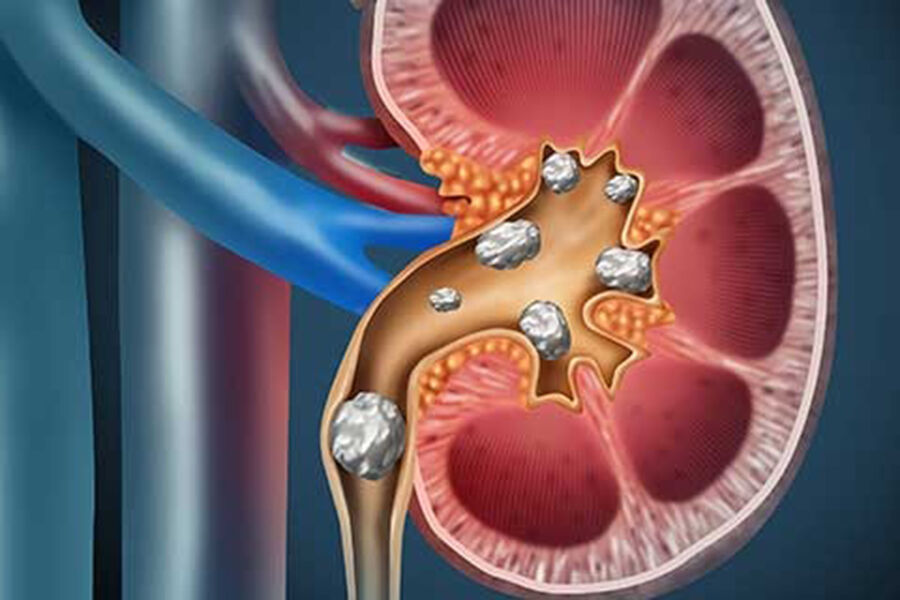

«Люди, в отличие от рептилий, выводят азотистые отходы в жидком виде — через мочевину, аммиак и мочевую кислоту. Но если концентрация мочевой кислоты становится слишком высокой, она образует кристаллы в суставах или почках, вызывая подагру и камни», – уточнили ученые.

Ученые предполагают, что некоторые свойства мочевой кислоты, которые помогают рептилиям обезвреживать аммиак, могут играть защитную роль и у человека, но эту гипотезу еще предстоит проверить. Исследователи считают, что понимание механизмов этого процесса со временем может привести к созданию новых методов лечения заболеваний, связанных с нарушением обмена мочевой кислоты.

Ранее был назван неожиданный фактор риска образования камней в почках.